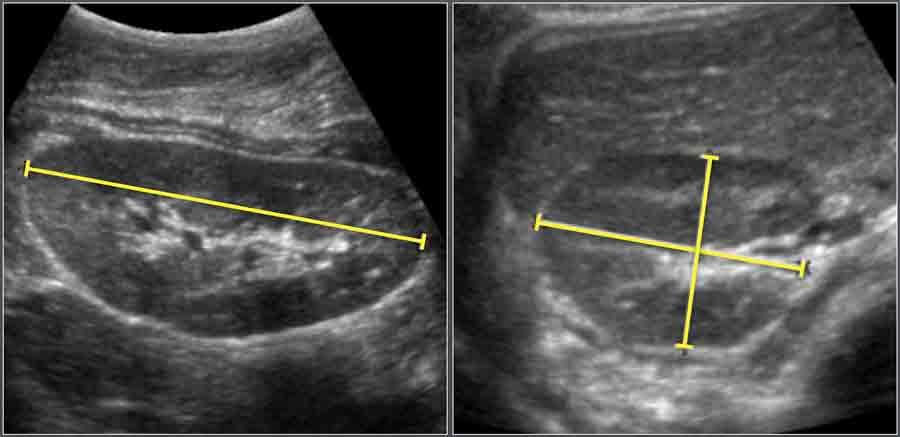

Thận

Trẻ sinh non và trẻ đủ tháng

Vật liệu và Phương pháp

Đánh giá siêu âm được thực hiện trên 261 trẻ sơ sinh khỏe mạnh.

Kích thước đầu-đuôi của mỗi thận được đo bằng siêu âm tiêu chuẩn.

Đo chiều dài thận sơ sinh trên siêu âm.

Ở trẻ sơ sinh, nhu mô thận thường có độ hồi âm cao hơn nhu mô gan, đây là hình ảnh bình thường ở lứa tuổi này.